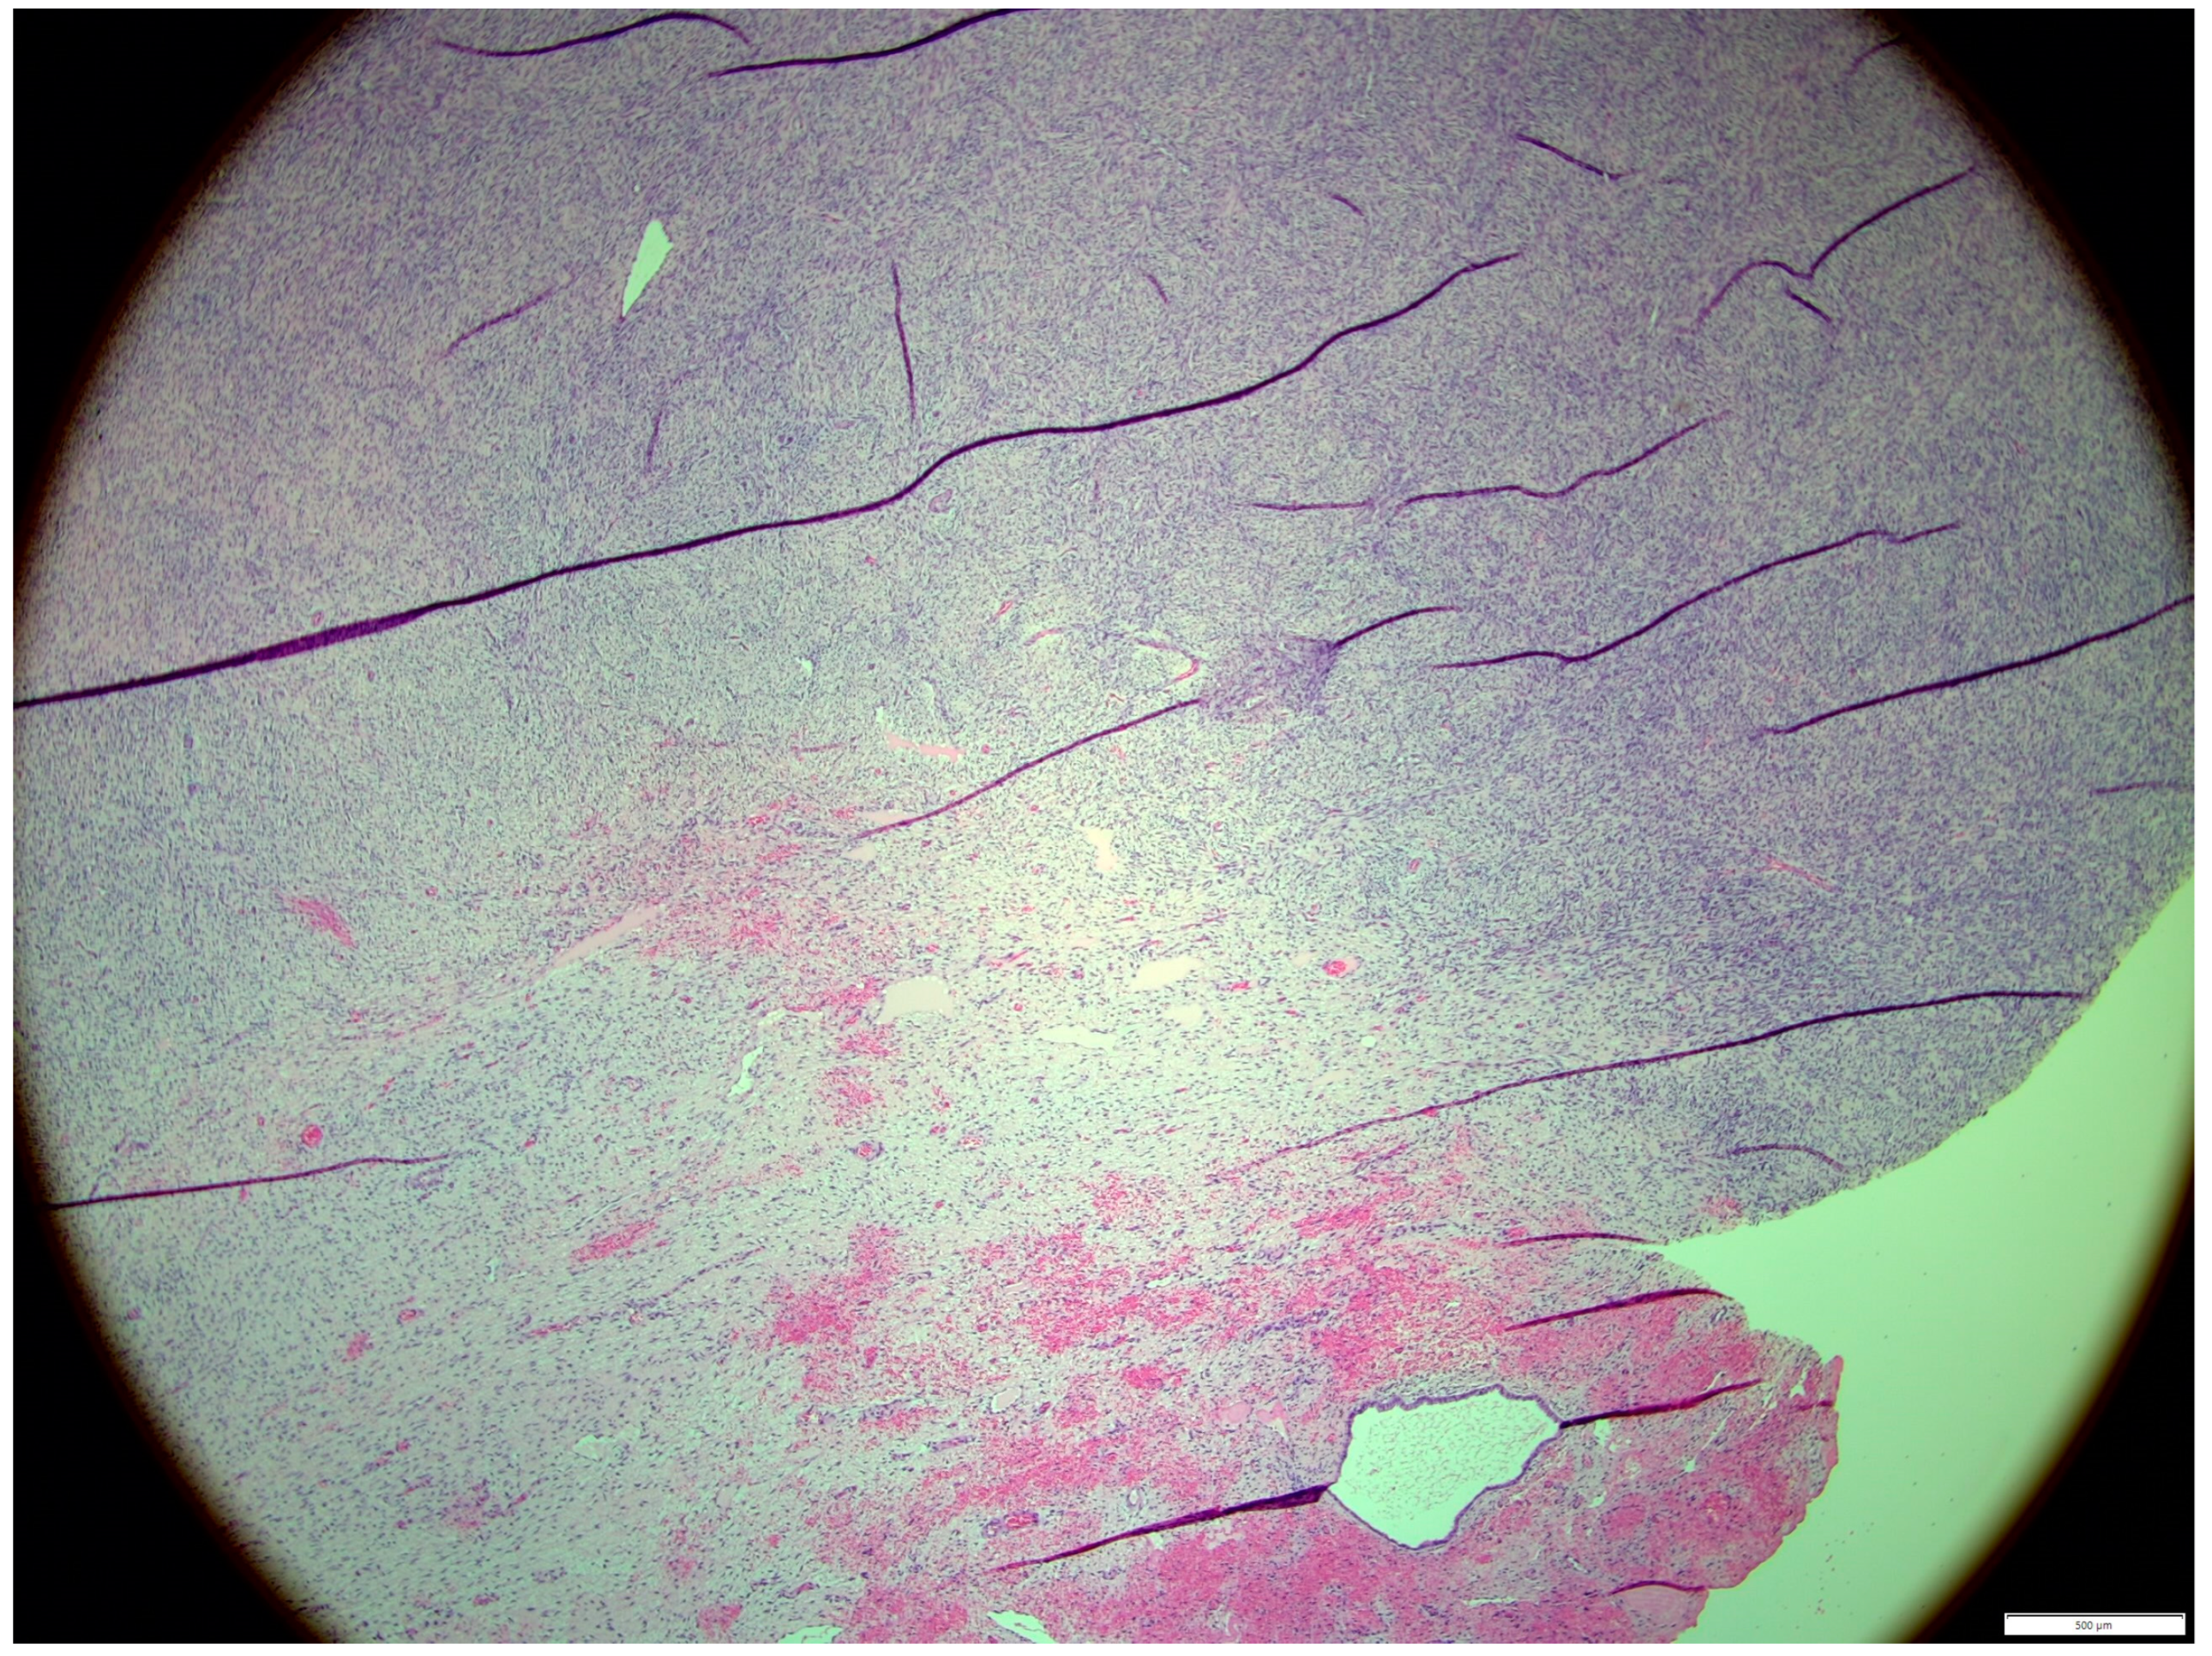

Histologically, both tumor areas were distinctly different from each other (Figure 7 and Figure 8). In the obtained sample for histological examination, the portion of the thecoma was significantly lower (Figure 9). Marked hemorrhage (but not blood-filled lacunae) and very sparse granulation-type connective tissue were observed at the border between both tumor tissues (Figure 10). Hemorrhagic blood masses infiltrated a larger part of the thecoma tissues. A single cystic structure lined with columnar epithelium was found in the hemorrhagic zone, with a very sparse amount of mucus-like material in the lumen (Figure 11).

Figure 9. The portion of the thecoma was significantly lower. HE, 100× magnification.

Animals 14 01307 g009